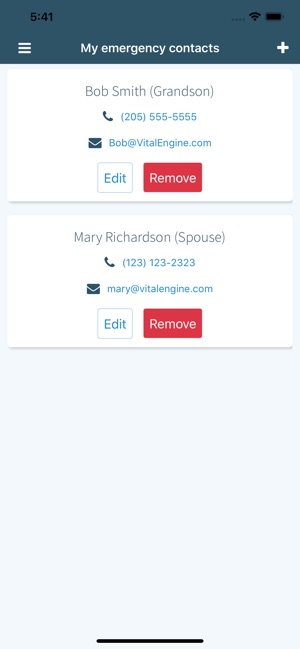

- Designate emergency contacts.